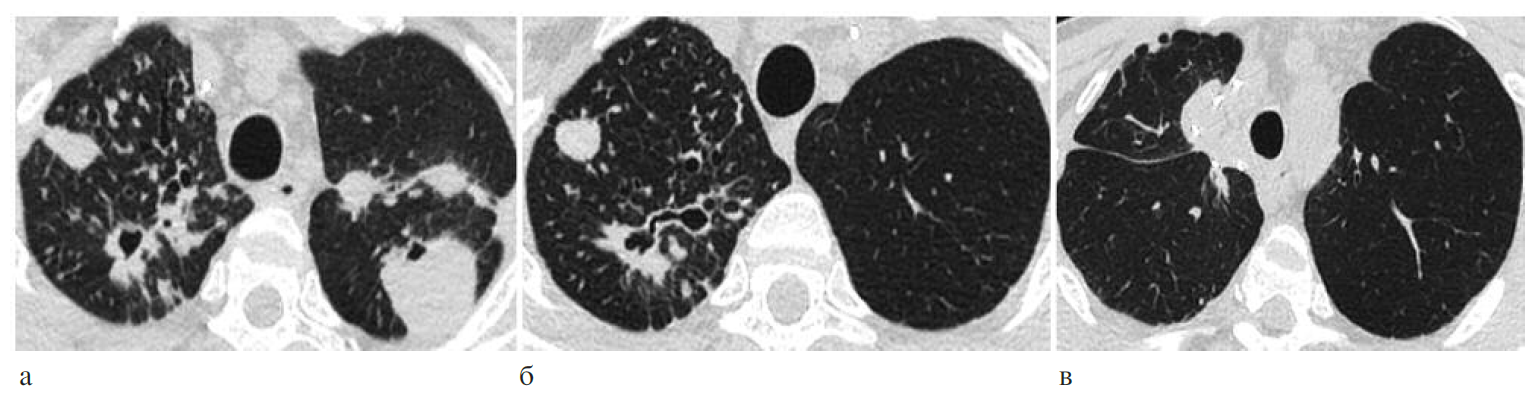

Больной Р., 38 лет. Анамнез: ВИЧ-инфекция с 2012 г., АРТ не получал из-за достаточно высокого иммунного статуса. Диссеминированный туберкулез легких выявлен в 2013 г., МБТ+, МЛУ (устойчивость к изониазиду, рифампицину, стрептомицину). Лечение по IV режиму химиотерапии на протяжении 18 мес с положительной клинико-рентгенологической динамикой, однако сформировались множественные туберкулемы верхних долей обоих легких с деструктивными изменениями. Поступил в 2014 г. для хирургического лечения. Иммунный статус: СD4+ лимфоциты 583 кл/мкл, вирусная нагрузка – 145 499 копий/мл (рис. 5, а). В течение месяца проведена интенсивная предоперационная подготовка с включением бедаквилина, линезолида и моксифлоксацина, затем выполнена этапная операция: сначала верхняя лобэктомия слева, затем через 4 нед справа (рис. 5, б, в). Послеоперационный период протекал без осложнений. При контрольном обследовании отмечены изменения показателей иммунного статуса: СD4+ лимфоциты снизились до 203 кл/мкл, при этом вирусная нагрузка также уменьшилась до 34 492 копий/кл. Через 2 мес после операции пациенту развернута АРТ. При динамическом наблюдении в течение 5 лет после операции рецидива туберкулеза не отмечено, течение ВИЧ-инфекции стабильное на фоне АРТ.

Рис. 5. КТ-исследование: а – до операции; б – после верхней лобэктомии слева; в – после верхней лобэктомии справа.